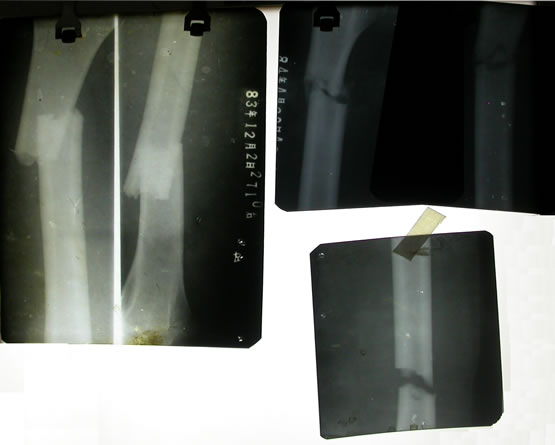

© Copyright2004 李氏骨伤科研究所 版权所有